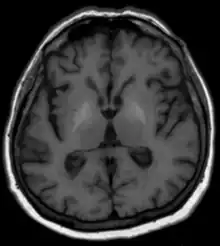

Les méthodes habituelles telles qu'analyses de sang, échographie et autres procédures d'imagerie par tomographie ainsi que la clinique[1] et, si nécessaire, une biopsie du foie avec examen histologique, sont disponibles pour diagnostiquer la maladie hépatique sous-jacente. En ce qui concerne la dégénérescence du cerveau, aucun changement n'est généralement visible sur la tomodensitométrie. L'IRM montre généralement une augmentation du signal dans les noyaux gris centraux sur les séquences natives pondérées en T1[1]. On soupçonne que la cause en est des dépôts de minéraux paramagnétiques, potentiellement réversibles après une transplantation hépatique[1],[2]. Les images pondérées T2 ne montrent généralement aucune anomalie. En termes de diagnostic différentiel, les changements de signal décrits ci-dessus sont parfois observés avec une nutrition parentérale à long terme mais également avec des calcifications idiopathiques. La maladie de Wilson doit également être prise en compte dans le diagnostic différentiel[1].